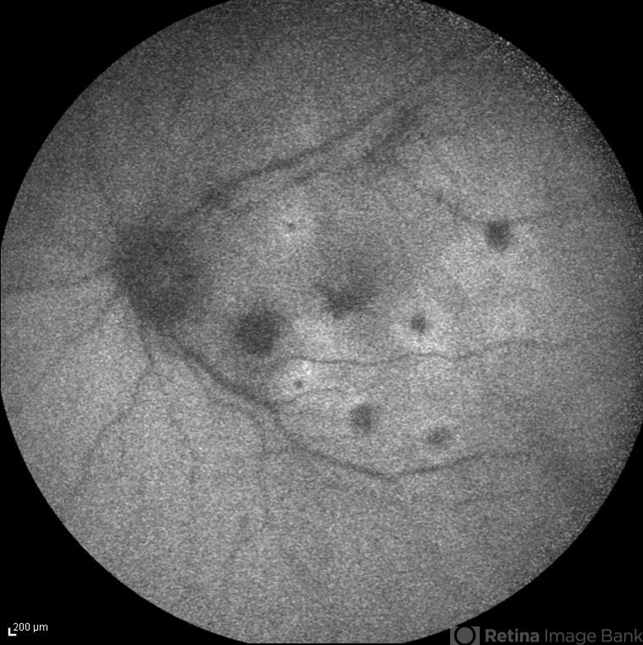

- infrared image, candida endophthalmitis, endogenous endophthalmitis

- Infrared image of the left eye of a 45-year-old diabetic man with the history of urinary tract infection. The most probable diagnosis was candida endogenous endophthalmitis.